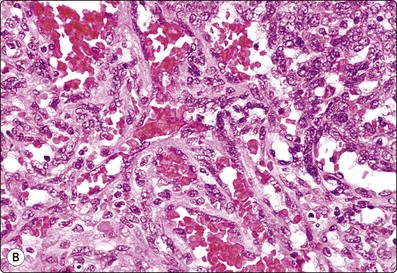

image image

Fig. 10.16 Hepatocellular carcinoma

A reticulin stain on cell block sections may highlight (A) widened trabeculae and/or acinar structures (Reticulin, HP); (B) reduced or absent reticulin (cell block reticulin, HP).

Smears are typically cellular with large fragments, clusters and dispersed cells (Fig. 10.14). Cell groupings are classically trabecular (Fig. 10.15A), particularly in better-differentiated tumors. Acinar arrangements may be seen in up to 40% of HCC (Fig. 10.15B).72 With decreasing differentiation, smaller sheets and single-lying cells become more frequent. A reticulin stain on smears or cell block material may highlight the widened trabeculae and/or acinar structures or the reduced or absent reticulin (Fig. 10.16). Endothelial relationships to HCC cell groups are an integral part of the diagnosis. Endothelial cells of sinusoidal capillaries may traverse (Fig. 10.17) or enclose (Fig. 10.18) trabeculae or separate tumor cell groupings.128 This important diagnostic criterion is diminished and then lost with decreasing differentiation.

Prior to embarking on costly immunotests, a reticulin stain can highlight loss of a normal sinusoidal pattern and shows either widened trabeculae, rounded islands and pseudoglands or just a reduction or total absence of reticulin and distinguish benign from malignant liver lesions (see Figs 10.6 and 10.16).77-79120